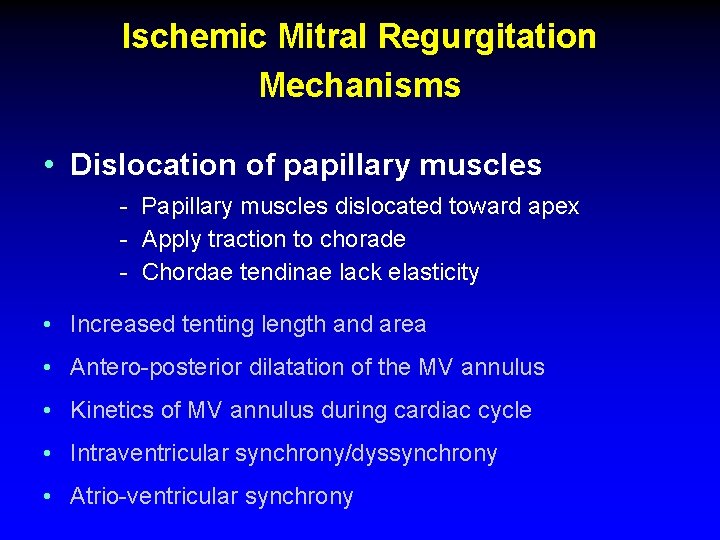

Ischemic Mitral Regurgitation Mechanisms • Dislocation of papillary muscles • Increased tenting length and area • Antero-posterior dilatation of the MV annulus • Kinetics of MV annulus during cardiac cycle • Intraventricular synchrony/dyssynchrony • Atrio-ventricular synchrony

Ischemic Mitral Regurgitation Mechanisms • Dislocation of papillary muscles - Papillary muscles dislocated toward apex - Apply traction to chorade - Chordae tendinae lack elasticity • Increased tenting length and area • Antero-posterior dilatation of the MV annulus • Kinetics of MV annulus during cardiac cycle • Intraventricular synchrony/dyssynchrony • Atrio-ventricular synchrony